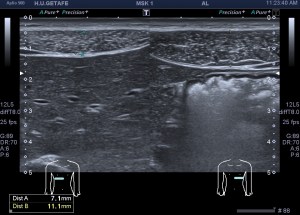

Cuando hice el corte longitudinal de la vesícula pude ver hasta tres patologías distintas, una adeomiomatosis (sin artefacto en cola de cometa), una litiasis vesicular y barro biliar, 2,3 y 4 respectivamente.

La adenomiomatosis, como un aumento de la ecogenicidad y el tamaño de la pared vesicular, la litiasis como una estructura hiperecogénica con sombra acústica posterior y el barro biliar, hiperecogénico rellenando toda la estructura ovoidea de la vesícula.

El cuello vesicular estaría afectado por la adenomiomatosis, el cuerpo por la litiasis y el barro ocuparía el fundas vesicular.

Para el estudio de la adenomiomatosis es obligado que el foco esté situado en la línea de interés, eso hará que las imágenes sean más nítidas y podamos estudiar dicha ecoarquitectura y su patología convenientemente.

Debemos observar si existiese líquido perivesicular, o signos de colecistitis. En este caso, la paciente, con estas tres patologías ya iba bien servida.